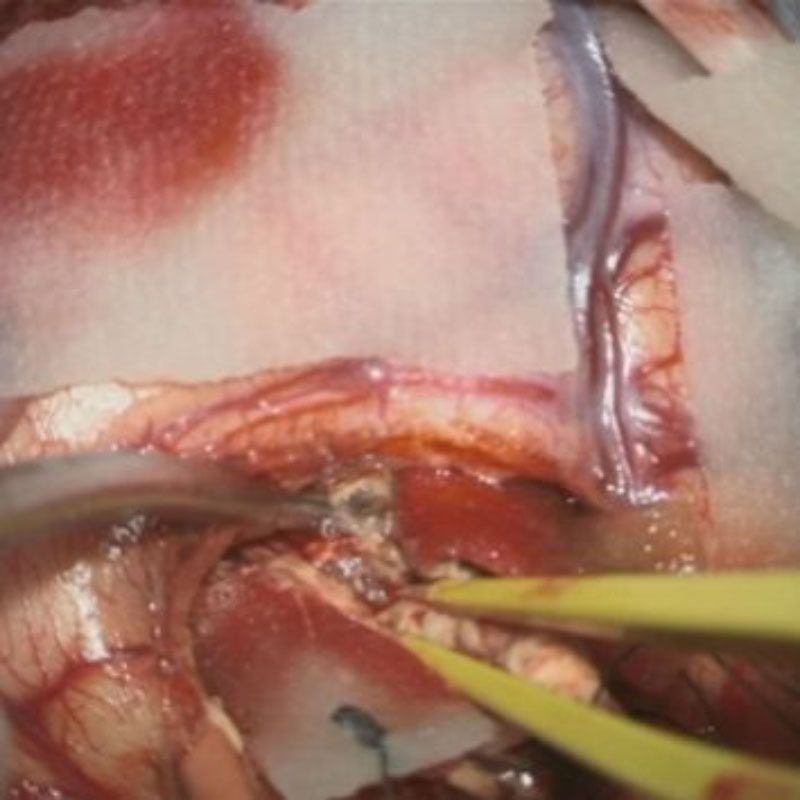

術中写真

摘出 中